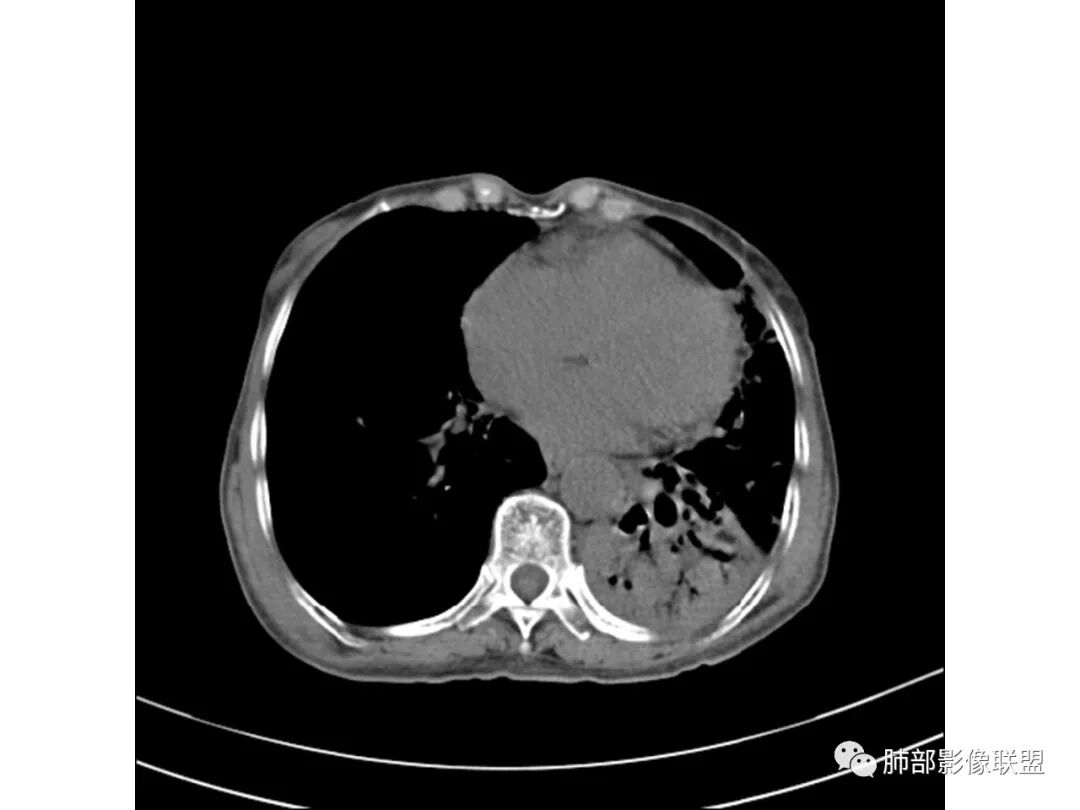

这些应该是胸水

支气管扩张、扭曲成团,附近钙化灶

纵膈也左移了

这例左下叶的体积是整体缩小的,左下叶的支气管主干稍微小一点点,然后左上叶的下舌段也有类似的病灶,然后我们看到一团乱的支气管扩张,但它有特点,边缘凹凸不平。那什么样的支气管扩张边缘会如此凹凸不平呢,等我截个图:

看最后一幅图,上面这个支气管,有可能是淋巴瘤,为什么?他的支气管稍扩张,直达远端、实变。

首先这幅图支气管很多地方是扭曲的,远端扩张的特别厉害。如果是肿瘤,首先考虑淋巴瘤,因为支气管可直达远端,稍扩张,但是它的前提是周围要实性占位的,而且它不会这样扭曲变形。我们看这个病例的支气管扩张,它支气管扩张占大部分区域,中间稍有些实性的结构,这就不符合了。这幅图你会发现所有支气管都是扩张的,实性部分偏少,外围胸水。所以我更倾向慢性炎性病变,能够引起支气管扩张的炎性病变有哪些?结核?NTM?支扩伴感染?大方向是慢性炎性病变。这些左下肺播散出来的病灶,咳中等量黄浓痰,我考虑还可能合并细菌感染。